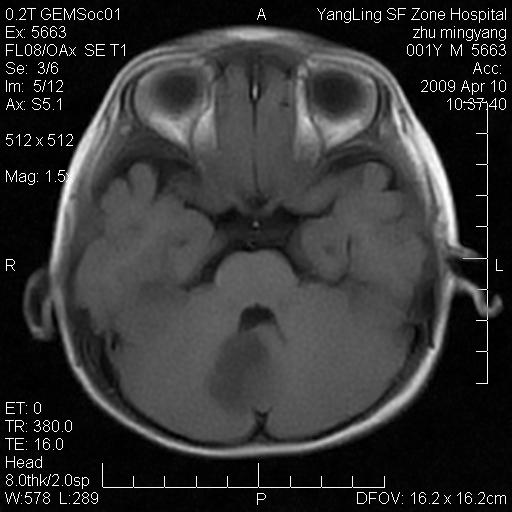

患者:1岁半,两天前外伤收住我院,ct检查小脑占位

考虑星形细胞瘤,建议增强

髓母细胞瘤或血管母细胞瘤,增强后可以鉴别;影像资料见 <。鱼博浪老师的《中枢神经系统ct与mr鉴别诊断》 小脑部肿瘤章节。

髓母细胞瘤或血管母细胞瘤!支持!

支持考虑髓母细胞瘤

考虑----髓母细胞瘤可能性大

考虑髓母细胞瘤或室管膜瘤。

支持髓母细胞瘤。

考虑髓母细胞瘤。

考虑髓母细胞瘤或星形细胞瘤

考虑髓母细胞瘤.

考虑髓母细胞瘤可能性大。

小脑肿瘤.考虑髓母细胞瘤可能.

就病灶部位及临床资料首先考虑髓母.